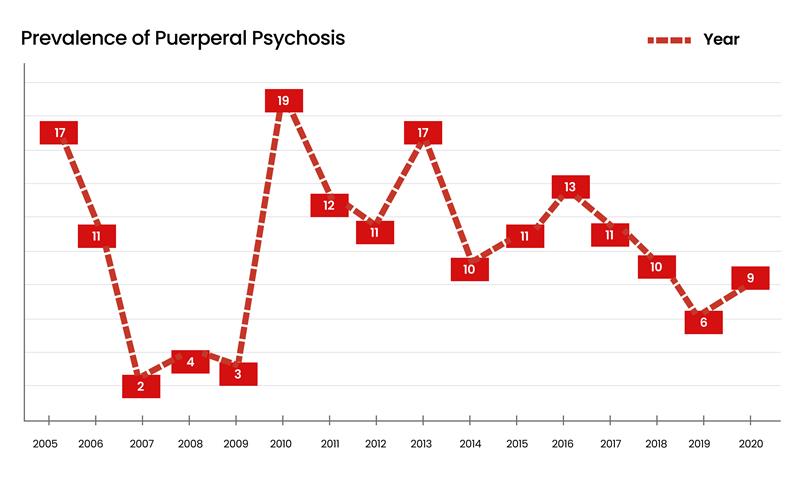

Psychiatry | Dec 16, 2024

Socio-Demographic Determinants of Prevalence of Puerperal Psychosis Among Postpartum Mothers Attending Neuropsychiatric Hospital Remigio, Portharcourt

Postpartum mothers attending the neuropsychiatric hospital Remigio have suffered silently from puerperal psychosis in previous years and even now, due...Read More